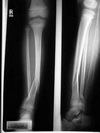

Tibia and fibula fractures